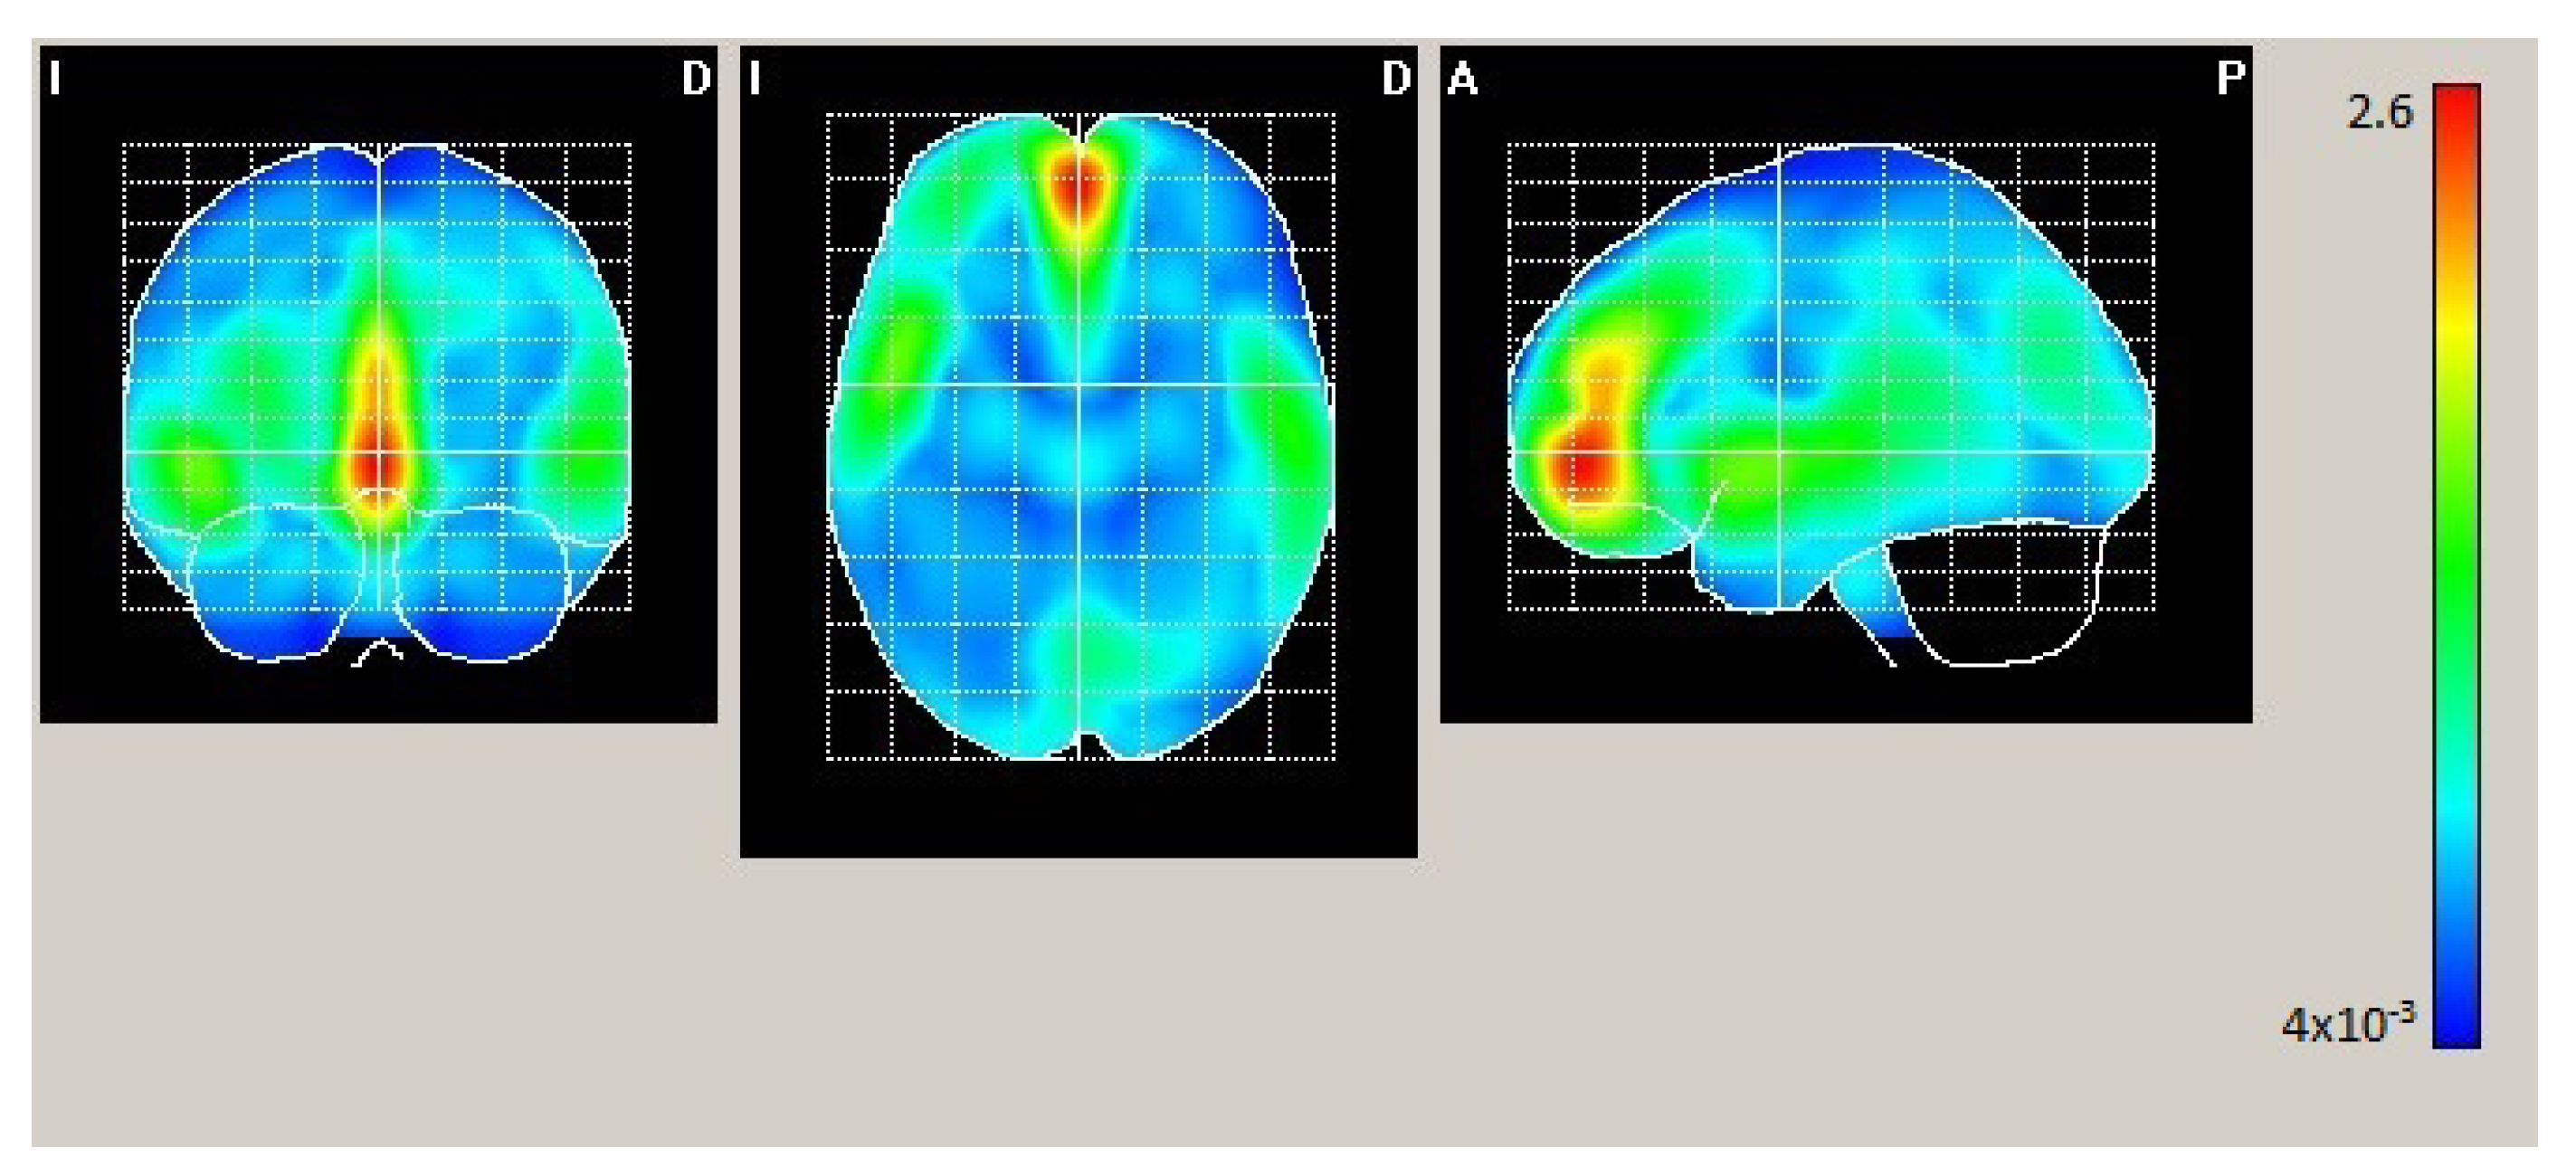

In Condition 1 (hearing participants with neither auditory nor tactile stimulation), as shown in Figure 2 and Table 2, maximum statistically significant activation was found in the bilateral middle frontal orbitofrontal, bilateral superior frontal gyrus, and left cingulum.

Figure 2.

Mean electrical maps for Condition 1 (hearing participants, audiovisual stimulation). Maximal intensity projection areas are displayed in yellow/red color. SPMs were computed based on a voxel-by-voxel Hotelling T2 test against zero.

Table 2.

Condition 1. Brain XYZ coordinates of the maximum in each of the activated areas.